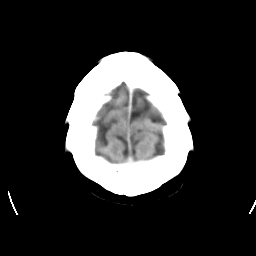

CT Study #1 -- Slice #22